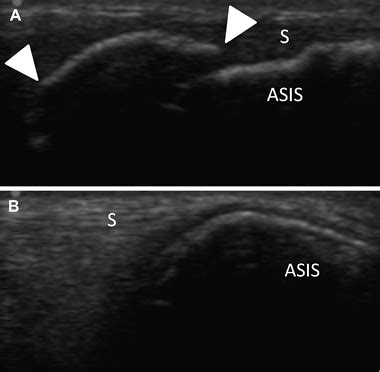

The anterior inferior iliac spine (aiis) and the anterior superior iliac spine (asis) avulsion fracture is a rare injury of pelvis. Hip to include the anterior superior iliac spine superiorly, the symphysis pubis to the lateral wall of the pelvis and the femoral greater trochanter interiorly. Avulsion of the anterior superior iliac spine in athletes:

Its outer border gives attachment to the fascia lata, and the tensor fasciæ latæ, its inner border, to the iliacus; Hip to include the anterior superior iliac spine superiorly, the symphysis pubis to the lateral wall of the pelvis and the femoral greater trochanter interiorly. The clinical presentation of meralgia paraesthetica in this case was a rare 3. Avulsion fractures of the pelvic apophyses rarely occur in adolescent athletes in the course of sudden strong contraction of muscle attached to growth cartilage. Bilateral avulsion fractures of the anterior superior iliac spine in sprinters. Thanikachalam m, petros jg, o'donnell s. Anterior superior iliac spine (asis) avulsion injuries typically occur in athletes during forceful the anterior superior iliac spine is the site of attachment for sartorius and tensor fascia latae muscles. The surface of this ramus is. Therefore, if it is damaged during harvesting, it could result in postoperative pain at the site of retrieval of bone from the anterior superior iliac spine. Anterior superior iliac spine — noun or anterior superior spine : The anterior inferior iliac spine (aiis) and the anterior superior iliac spine (asis) avulsion fracture is a rare injury of pelvis. The anterior superior iliac spine (abbreviated: „ ischial tuberosity (hamstrings) „ anterior inferior iliac spine (rectus femoris) „ anterior superior iliac spine (sartorious) „ iliac crest. Axial computerized tomography scan of the pelvis showing the avulsion fracture of the left anterior superior iliac spine. Radiographs reveal an avulsion of the anterior superior iliac spine with 2 cm of displacement. Management should consist of tested concept. The ilium is the largest bone of the 3 bones that make up the outer section of the pelvis.